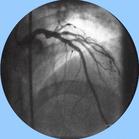

冠脈造影心電圖:外科治療的患者中約半數心電圖完全正常,其餘患者顯示右心室或左心室負荷增重。

心導管檢查和心血管造影:心導管檢查、主動脈和選擇性冠狀動脈造影既可測算左向右分流量和測量右心繫統壓力,又可顯示瘺的部位及冠狀動脈情況,是確診本病和設計手術治療方案所必須進行的檢查。

冠狀動脈瘺分流部位血氧含量增加,在臨床上常考慮為動脈導管未閉、室間隔缺損及主動脈竇瘤破裂等,因此當其他臨床資料不典型時應考慮有冠狀動脈瘺的可能。逆行性升主動脈造影及冠狀動脈造影,可顯示冠狀動脈瘺的起始、終止部位及走行範圍等。